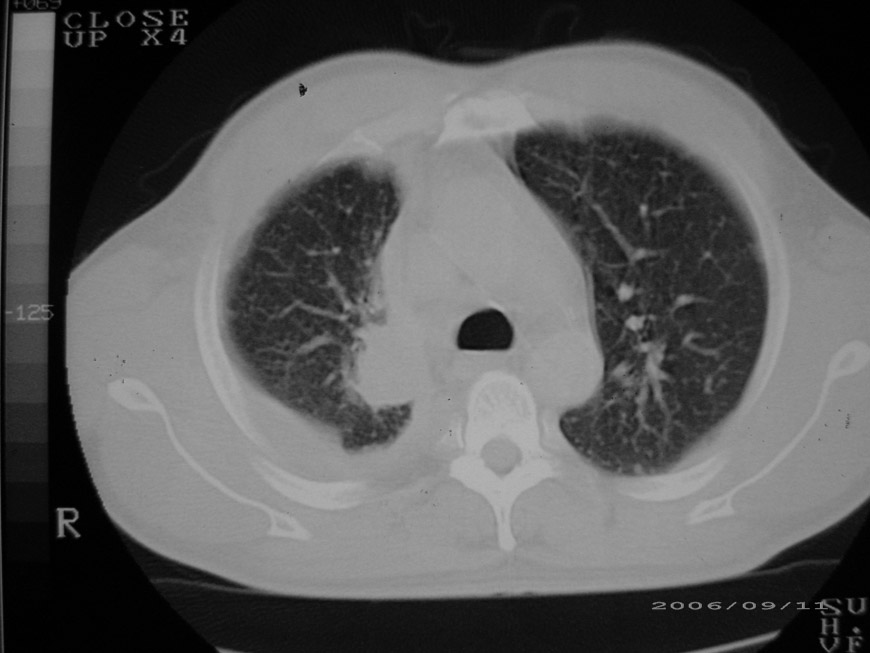

以下是引用守望可可西里在2006-9-11 15:29:00的发言:[br][br] ct平扫表现:右侧胸膜腔缩小,积液,胸膜增厚且不均匀、不规则,以纵隔胸膜增厚为主,边缘呈锯齿状,并见附壁内突之结节状肿块影。右肺含气量减少,纹理聚集,右肺门中下部见数个肿大的淋巴结。纵隔无移位,内未见明显肿大淋巴结,双侧主支气管以及各叶、段支气管比较通畅。。[br] 考虑:右侧胸膜恶性间皮瘤,伴肺门淋巴结转移。